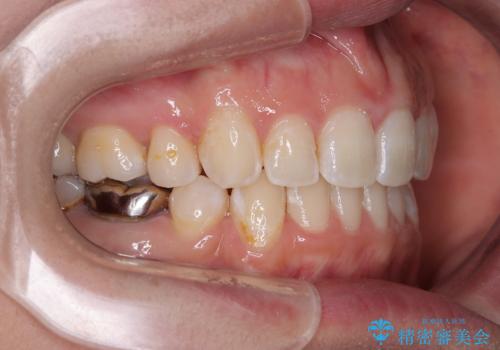

- 口元の突出感と奥歯のむし歯を気にして来院された患者様です。

奥歯の虫歯は事前に矯正治療用の仮歯に置き換えて矯正治療を行い、装置除去後にセラミッククラウンにて補綴治療を行うこととしました。

通常は上下左右の第一小臼歯4本を抜歯することになりますが、左側下顎の第二小臼歯は既に根管治療をされており、予後が良くないとのことでこの歯を抜歯し、ワイヤー装置にて矯正治療を行うこととしました。